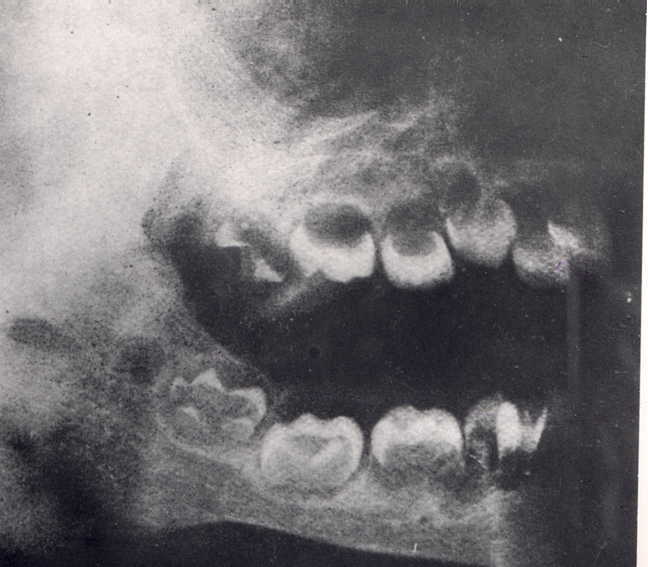

X-quang hàm trên và dưới trẻ sơ sinh | ![]()